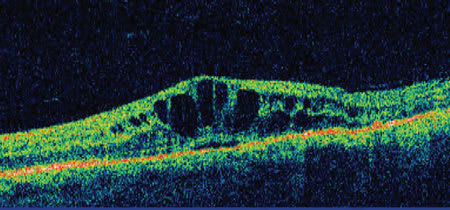

▪ Optical coherence tomography. Optical coherence tomography (OCT) is currently one of the most important imaging techniques used in the study of uveitis. It enables imaging of the optic nerve head, nerve fiber layer, retina, choroid, and the vitreoretinal interface in a noncontact and noninvasive manner. It can be repeated as often as necessary since there are no serious side effects in OCT testing. OCT can be used to quantify macular thickening and thus is an excellent way of diagnosing CME and monitoring the effectiveness of treatment (Figure 6).41,42 OCT can detect vitreoretinal interface disorders such as epiretinal membranes, macular holes, and vitreomacular traction, which can assist in management.43-45 OCT is also valuable in the study of the different types of retinal detachment and the role, location, and density of an associated exudate. The most important limitation of OCT is its reliance on relatively clear media for useful images. A second factor limiting OCT’s utility is the need for patient cooperation with fixation and control of eye movements. These limitations may prove difficult for photophobic subjects.

Figure 6. Optical coherence tomogram through fovea in patient with cystoid macular edema.